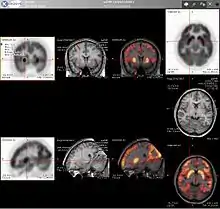

نتیجهٔ ترکیب سیستمهای پت و سی تی اسکن تصویر ساختاری-دگرگشتی بالا میباشد.